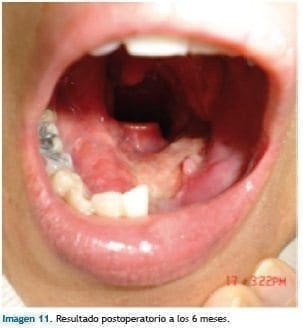

Radioterapia postoperatoria con acelerador lineal en Centro Oncológico Javeriano (Imagen 10). Resultado postoperatorio a los 6 meses (Imagen 11).

En este periodo la paciente logra emisión de palabras comprensibles, con adecuada comunicación.